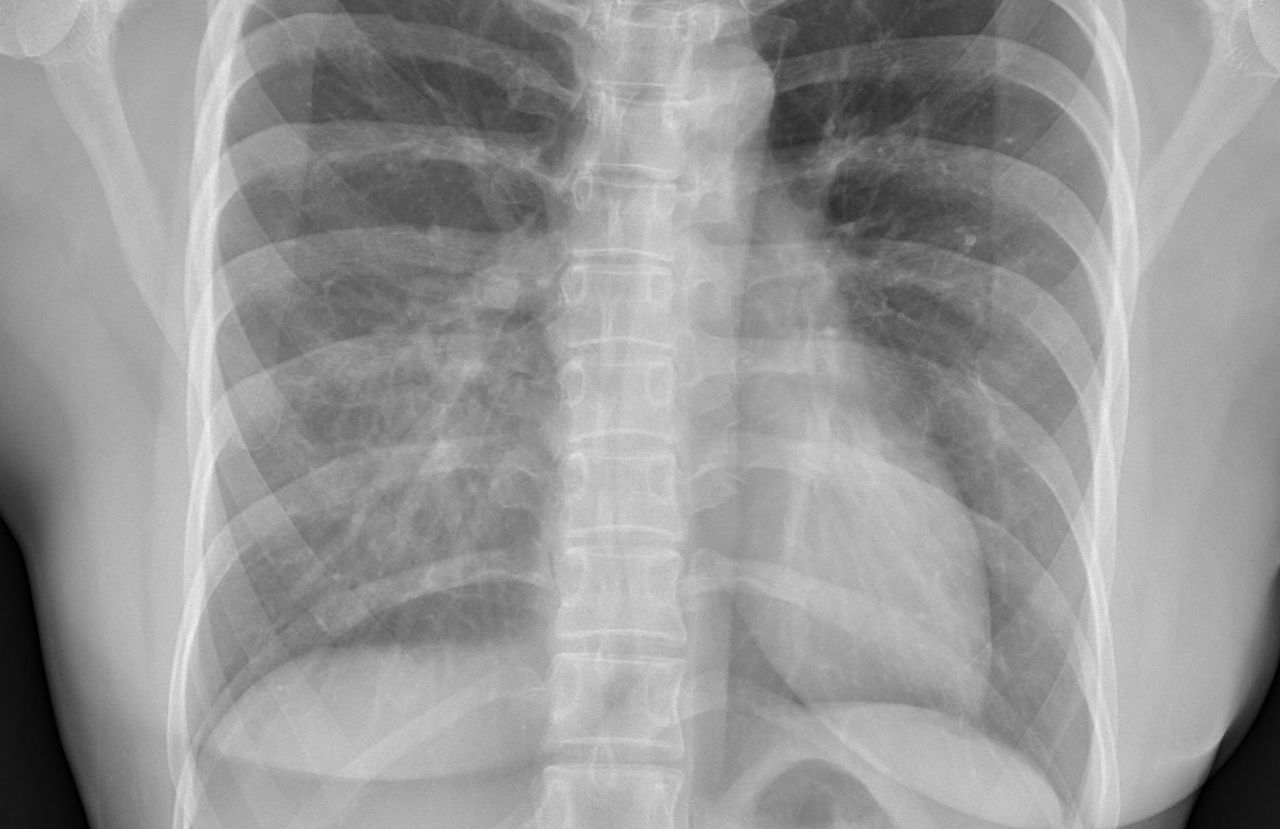

▲患者的X光片。(圖/翻攝蘇一峰臉書)

胸腔科名醫蘇一峰分享,一名40歲女性容易喘一陣子了,X光長這樣,讓大家猜看看是什麼問題,答案是「漏斗胸」(胸廓變形),「因為肺被擠壓,所以看起來肺變白,看起來像肺炎。」

蘇一峰在臉書貼出患者的X光片,「其實我靠這張X光就可以診斷了,大家覺得是肺炎嗎?不知道AI會不會!?」

蘇一峰後來公布答案,「這個女性病人答案是「漏斗胸(胸廓變形)」,完完全全沒有肺炎喔,你猜對了嗎?」

蘇一峰解釋,漏斗胸胸廓變形的患者,因為肺被擠壓,所以看起來肺變白,看起來像肺炎;此外,還有一個重要的判斷特點,病人的肋骨在X光下面比較呈現直角轉彎,一般人X光下的肋骨是120度轉彎,但是這種漏斗胸胸廓變形的人,各個肋骨會90度彎曲。